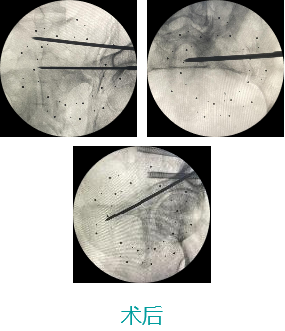

天玑II 辅助骶髂螺钉(S1-S2)、前柱顺行经皮空心螺钉内牢靠术

基本情形:患者男,,,,,,61岁,,,,,,骨盆骨折

机械人辅助优势:天玑II接纳C臂跟踪器来完成图像收罗和配准,,,,,,优化手术流程

病例泉源:北京积水潭医院